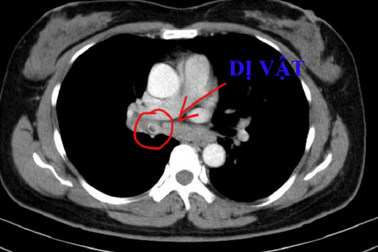

Hy hữu lưỡi câu, cục sắt nằm trong phế quản bệnh nhân tâm thầnSáng 9/8, tin từ Khoa Nội tổng hợp, Bệnh viện Đa Khoa tỉnh Quảng Nam cho biết, các y, bác sĩ của Khoa vừa nội soi gắp thành công các dị vật phức tạp nằm hai bên phổi của một bệnh nhân tâm thần.